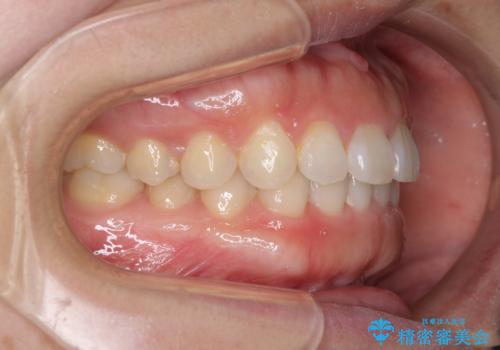

- 前歯のデコボコを治したいとのことで来院された患者様です。

上下顎ともに歯列全体の側方拡大とIPR(歯と歯の間を削る)によってデコボコが解消するように設計し、インビザラインにより治療を行うこととしました。

後方移動に際し、残っていた上顎の親知らずを抜歯することとしました。

1日22時間の装着時間をしっかり守ってくださったので、1年程度で治療を終えることができました。

1セットのマウスピースで概ね治療を終えたのですが、前歯僅かな叢生が残ったため、2セット目のマウスピースで仕上げました。

気にしていた口元の印象が改善され、患者様には大変満足していただきました。